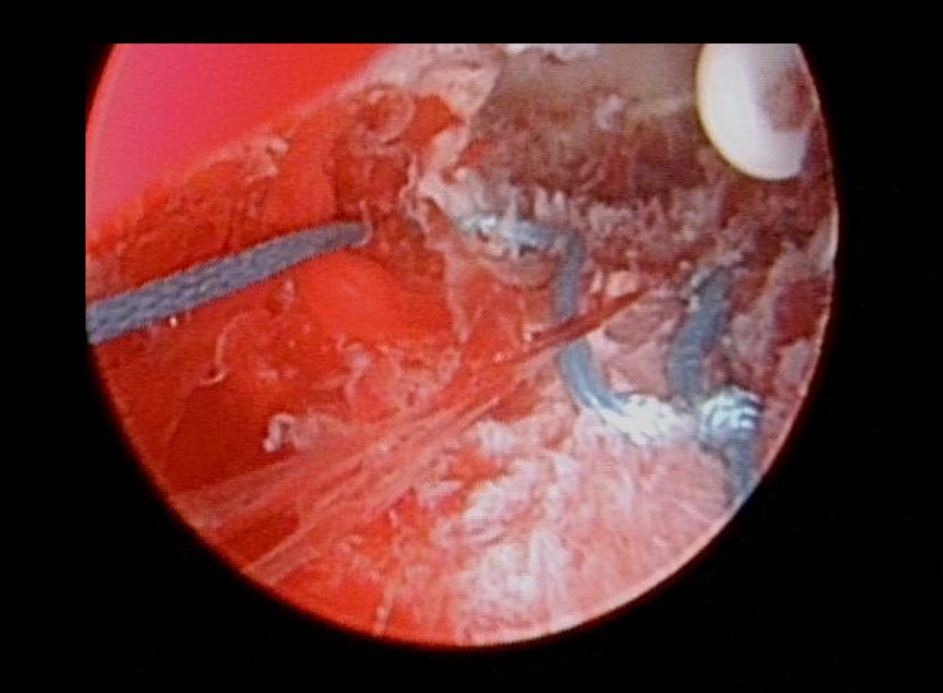

✦考虑到患者曼月乐环治疗腺肌症有效,病灶比较局限,拟行子宫腺肌症病灶射频消融+曼月乐环缝合固定术。